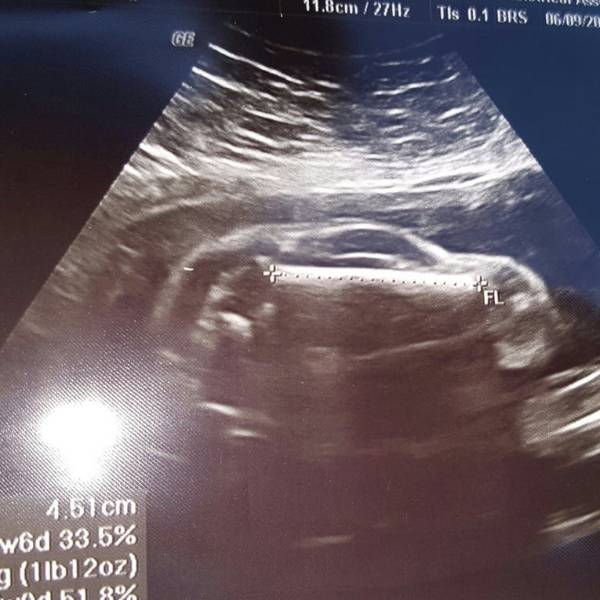

¿Un bebé o un auto deportivo? La sorpresa que dejó un ultrasonido

Uno de los momentos más emocionantes para una pareja es conocer el sexo de su hijo. Sin embargo, una pareja se llevó una gran sorpresa al mirar el monitor y ver que lo que mostraba el ultrasonido.

Lejos de parecerse a un bebé, la pantalla mostraba lo que parecía ser un auto deportivo dentro del vientre de la mujer, que tenía 24 semanas de gestación.

La imagen del ultrasonido mostraba una misteriosa silueta con ruedas, un techo inclinado, una ventana e incluso algo que se asemeja a un pequeño volante.

La curiosa imagen, que se viralizó rápidamente, fue compartida por el padre del bebé en Reddit con el siguiente mensaje: “Mi mujer está embarazada de un auto deportivo”.